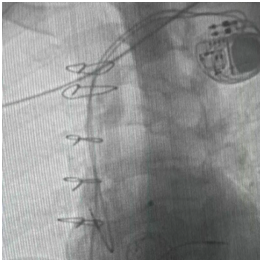

永久起搏器植入术

手术台上,心脏大血管外科陈文生团队通过细致的影像引导,将球囊送至原有瓣膜处进行扩张,随后将新的生物瓣精准释放在预定位置。最后,在心脏稳定的状态下,顺利植入了永久起搏器。整个过程中,患者生命体征平稳。

术后超声显示,李爷爷三尖瓣的返流量从“大量”降至“少量”,心脏血流得到根本改善。起搏器工作正常,心跳恢复稳定节奏。术后恢复顺利,水肿等症状明显消退,恢复情况良好。目前,李爷爷已康复出院。